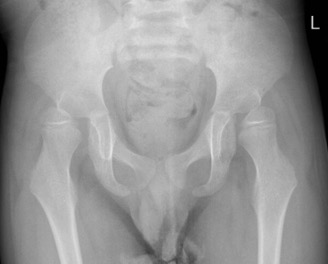

Subluxing hips

In the lower limbs, there is increased risk of hip dislocation and it is important that carers learn good hip health measures to ensure the hips remain in joint. The principle is to keep the hips wide spread (abducted), so the wheel chair should have a pommel and out of the wheelchair an abduction brace may be required until the hips are well developed. Hips which are already subluxing or dislocating require a surgical procedure to put them back in place. Failure to do so could lead to restricted movement, problems with perineal hygiene, pain and discomfort even on sitting, and eventually, in extreme cases, ulceration of the hip from the inside out.

Dislocated left hip